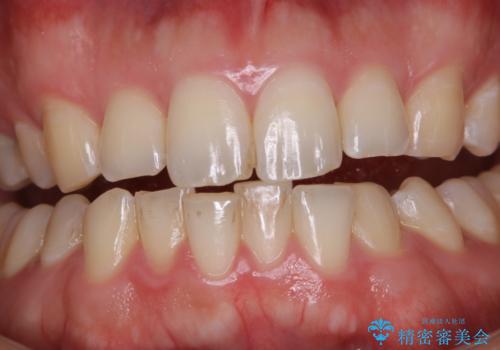

- 歯磨きをしても取れない汚れが気になるとのことで来院されました。PMTC60分コースを行いました。

着色や歯石は歯みがきで落とすことはできません。誤ったセルフケアを行うと、逆に歯の表面を傷つけてしまったり、トラブルを起こすこともあります。

着色や歯石が付着したままだと、居心地のよくなった細菌たちが口の中の栄養をたっぷり摂ってさらに付着しやすい状態となります。